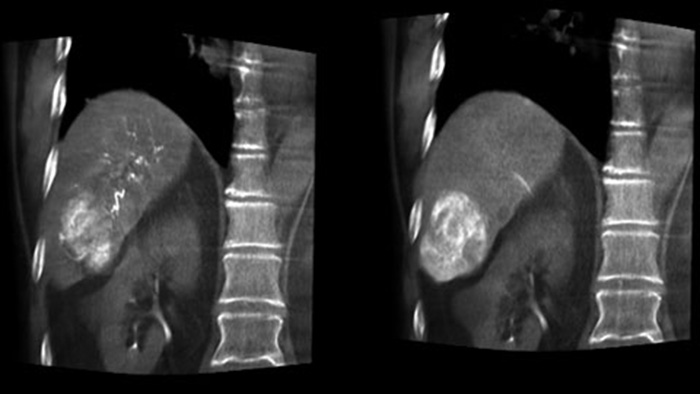

CBCT Dual permite la adquisición en 3D de una fase arterial para visualizar estructuras vasculares y una posarterial (fase retardada) para visualizar la acumulación del medio de contraste, en un solo paso automático5.

Dual View permite la visualización simultánea de dos conjuntos de datos de CBCT. Tanto la fase arterial como la fase retardada se pueden visualizar una junto a la otra o en una sola vista de superposición fusionada.